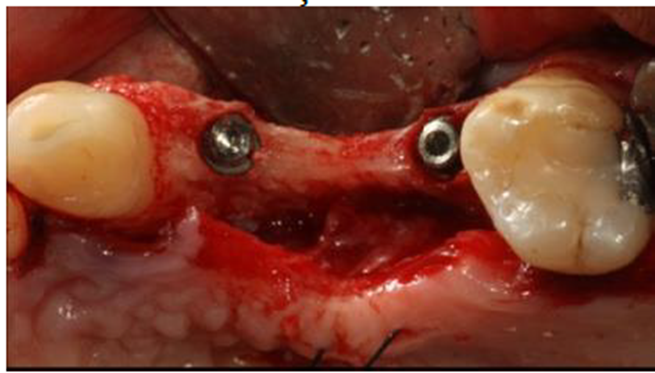

Foi realizado também um retalho total com relaxante distal na região do molar, seguido de um retalho dividido após o descolamento passar da gengiva inserida para permitir um fechamento primário sem tensão. A fresagem foi realizada com o sistema de osseodensificação (Neobiotech – Nova IM3 – Coreia do Sul). No implante proximal foram utilizadas fresas sequenciais (16 mm, cônica 16/28 mm e cônica 22/34 mm), conforme figura 5, para a instalação de um implante Maestro de 3,5 x 11 (Implacil De Bortoli – São Paulo – Brasil). O implante distal foi instalado utilizando o mesmo sistema de osseodensificação com as mesmas fresas anteriores, mais a fresa cônica 28/40 mm, permitindo a instalação de um implante Maestro de 4,0 x 9 (Implacil De Bortoli – São Paulo – Brasil).

Apesar da técnica de osseodensificação permitir a expansão do rebordo suficiente para a instalação das fixações, o aumento não foi suficiente para corrigir o tamanho da atresia (Figura 6).